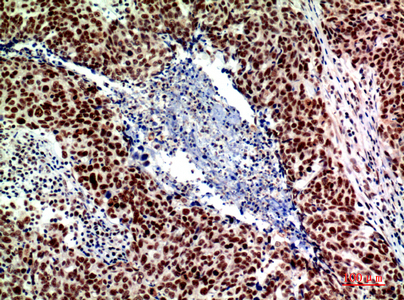

- Immunohistochemistry analysis of paraffin-embedded Human breastcancer using ASAH3L antibody.High-pressure and temperature Sodium Citrate pH 6.0 was used for antigen retrieval.